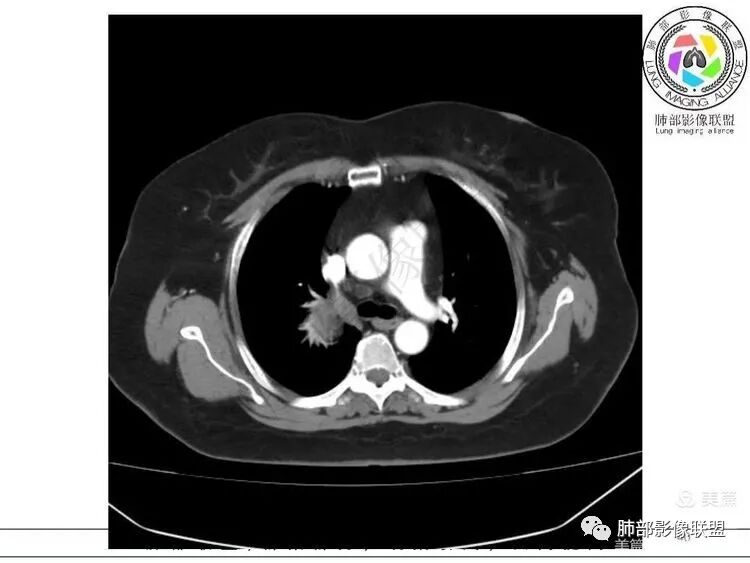

大雄:定位: 纵隔(往左推移气管 往前推移腔静脉 往下推移肺尖胸膜)定性: 良性(边缘光滑,与周围结构境界清晰,无侵袭性生长特点)特征:增强可见AB区(富细胞区与粘液区),延迟强化明显。考虑:神经鞘瘤 ,鉴别:SFTKing:纵隔偏良性肿瘤,与甲状腺无关。首先考虑神经鞘,其他如副节,SFT,巨淋巴待鉴别。飞鹰行动:右侧上胸腔近纵膈类圆形软组织占位,边界清晰光滑,内见囊变,增强渐进性强化,考虑来源纵膈的病变,神经鞘瘤可能,鉴别孤立性纤维瘤。小兜:右上纵隔椭圆形占位,胸膜掀起,肺组织受压,气管受压移位,考虑来源于纵隔,边缘光滑,增强扫描渐进性不均匀强化,内见大片无强化区,考虑为神经鞘瘤可能,鉴别SFT。陈学君:后纵隔占位,多发囊变,渐进強化,考虑鞘瘤,鉴别SFT红星:右上胸廓入口类圆形肿块,肺瘤界面清晰,肺支气管及血管受压,强化不均,片状楔形坏死,考虑来源纵隔占位,神经鞘瘤。鉴别STF、肉瘤?宇宙:右上后纵隔旁椭圆形肿块,边缘光整,向上突入颈根部,肺组织、血管及气管受压移位,密度不均匀,不均匀渐进强化,囊变,考虑神经鞘瘤,鉴别SFT

1. 右上胸廓入口区类椭圆形块影,边界清楚光整,纵向“嵌顿”于颈根部及上纵隔,向上推移右锁骨下动静脉,向外下方推移上肺胸膜及肺组织(肺血管、支气管),向前推移上腔静脉,界限清楚。

2. 块影不均匀轻度强化,可见较均匀实性区及液性密度区,未见积气、囊壁样结构、钙化或脂肪密度。可疑部分肋间动脉分支进入。

3.而“A/B”区密度特点以及上下径较大更支持神经鞘瘤,尽管这不属于好发部位。

神经鞘瘤是周围神经最常见的肿瘤,起源于神经鞘膜的施万细胞,生长缓慢,包膜完整,与起源神经紧密相连,绝大多数为良性,恶性罕见;纵隔内神经源性肿瘤90%发生于后纵隔,发生在交感神经链或肋间神经的椎旁;偶尔,神经鞘瘤可位于中纵隔或前纵隔,最常见的发生于迷走神经,其次是喉返神经、膈神经等。所以神经源性肿瘤很重要一点在于解剖,一般只要存在神经组织,都可以发生神经源性肿瘤;后纵隔神经鞘瘤最常见的位置是脊神经刚出椎间孔的位置,并沿着肋间神经分布,所以一般横径大,上下径小,而且来源于神经根的可呈哑铃状跨越椎管内外生长;而来源于前或中纵隔神经的迷走神经或喉返神经等是上下走形,所以神经鞘瘤常表现为上下径长;神经鞘瘤在病理上包括A区和B区,Antoni A区富含细胞,密度较高,Antoni B区含有较多粘液成分,密度较低,可见囊变、出血,如果出血,血肿可见机化、钙化。